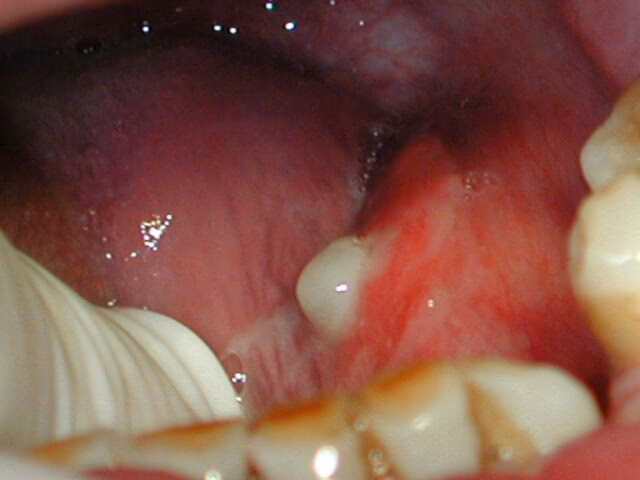

- Glándulas Sublinguales: Las más pequeñas de las mayores, situadas en el piso de la boca, bajo la parte frontal de la lengua.

Todas estas glándulas secretan saliva a la boca a través de pequeños conductos. Cuando algo interrumpe este proceso, ya sea una infección o una obstrucción, la saliva puede acumularse, provocando la inflamación característica.

Otra causa muy común de inflamación es la presencia de cálculos o depósitos minerales, conocidos como sialolitos, dentro de los conductos salivales. Esta condición se denomina sialolitiasis. Estos cálculos pueden formarse por la mineralización de cuerpos extraños, restos orgánicos y bacterias. Están compuestos principalmente por minerales como fosfato de calcio, magnesio, carbonato y amonio, junto con componentes orgánicos como carbohidratos y aminoácidos. Los sialolitos son más frecuentes en los conductos de las glándulas submandibulares, aunque también pueden afectar a las parótidas y, menos comúnmente, a las sublinguales y glándulas menores. Cuando un cálculo obstruye el conducto, impide el paso normal de la saliva, lo que lleva a su acumulación detrás de la obstrucción, causando dolor e inflamación de la glándula afectada. La inflamación muchas veces es visible en la cara o el cuello, dependiendo de la glándula.

El masaje puede ser una herramienta útil en el manejo de la sialolitiasis, especialmente para intentar desalojar cálculos pequeños o aliviar la congestión de la glándula. La técnica general implica la aplicación de calor húmedo en la zona para relajar los tejidos y luego un masaje suave pero firme. El masaje debe dirigirse desde la parte posterior de la glándula hacia la abertura del conducto en la boca, intentando literalmente "empujar" el cálculo hacia la salida. Por ejemplo, para un cálculo en la glándula submandibular, el masaje se realizaría bajo la mandíbula, desde atrás hacia adelante, en dirección al piso de la boca debajo de la lengua. Es importante ser gentil para no causar más dolor o irritación. Combinar esto con la estimulación de la producción de saliva (limón, caramelos) puede aumentar las posibilidades de éxito.